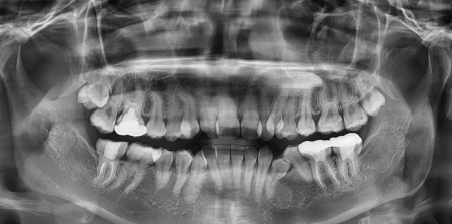

우체국 치아보험 특징 보장내용 보험료 계산 및 가입방법 등 우체국 치아보험에 대해 알아보겠습니다. 우체국 치아보험은 다양한 치과 치료 비용을 보장해주는 보험 상품입니다. 이 보험은 일반적인 치료부터 대비용 처치, 치과 교정까지 다양한 진료를 포함합니다. 가입 절차가 간단하며, 보험료도 합리적으로 책정되어 있어 많은 사람들에게 인기가 있습니다. 우체국 치아보험 특징 보장내용 보험료 계산 및 가입방법 알아봐요